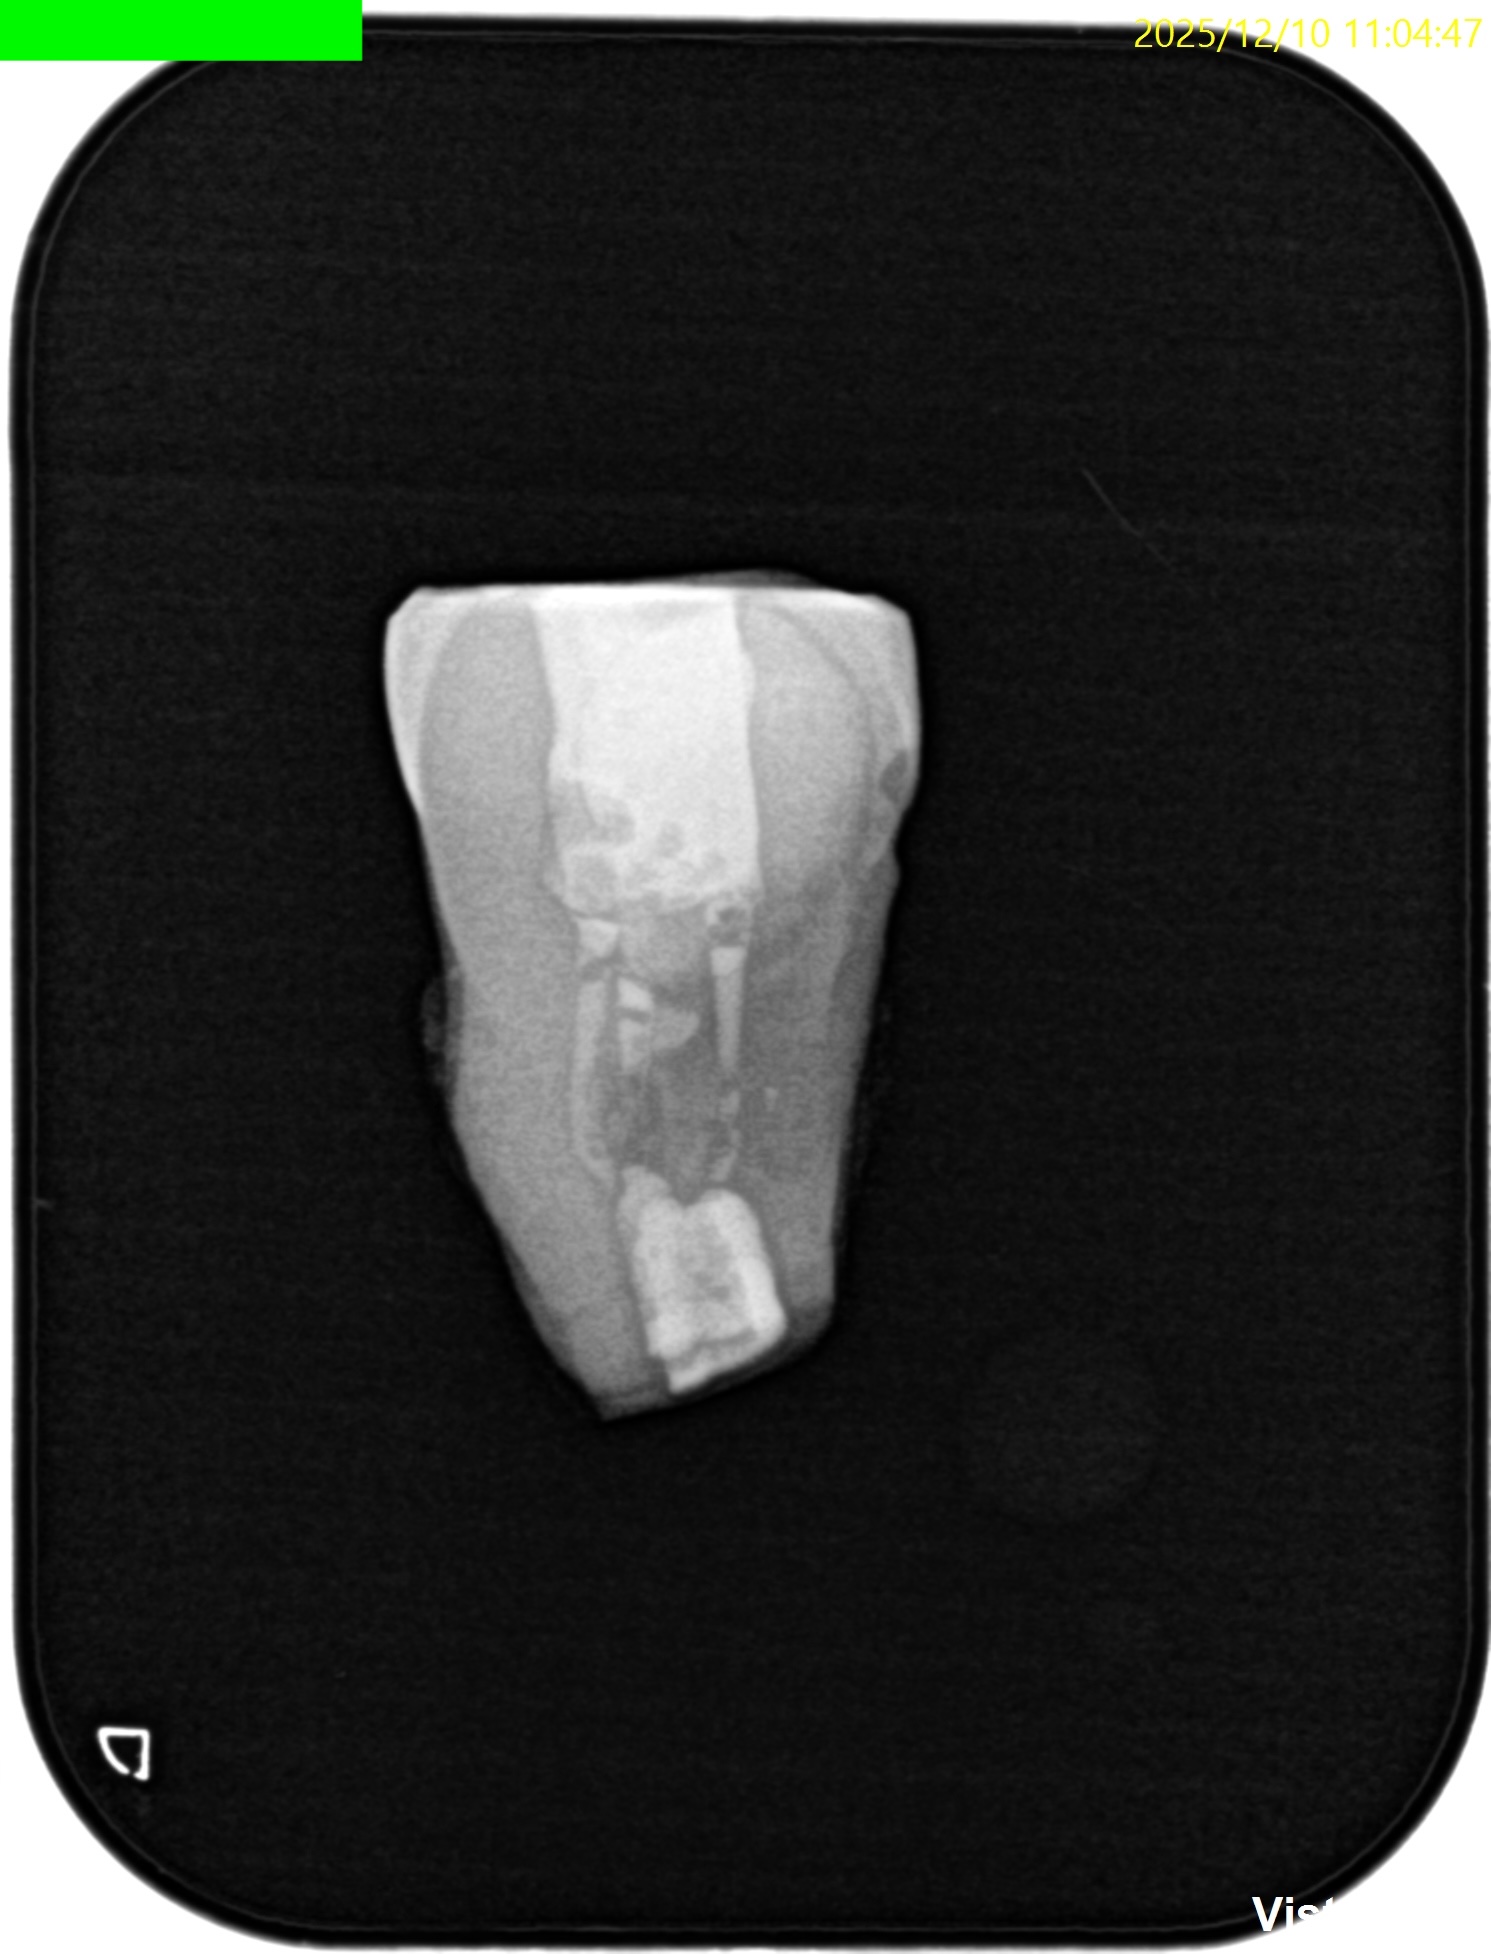

CBCT(2025.12.10)

ML

MB

D

遠心方向から見ると、

絶望的な状態であることがわかる。